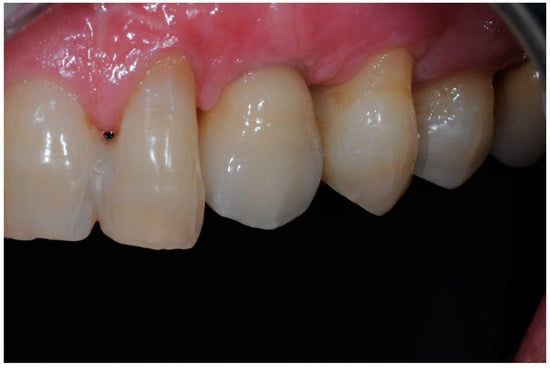

- Group 2: An implant-level impression adopting an open-tray impression technique was adopted using a polyvinylsiloxane impression material. After pouring the cast, a T-Base for ASCs was chosen, and a partially-veneered zirconia crown (limiting the veneering process to the vestibular surface) was realized. An angulated screw channel was designed, moving the access hole to the occlusal/lingual surface. At a second appointment, the crown was screwed to the implant and checked following the CMO (contact, margins, occlusion) acronym. The crown was then manually screwed to the implant and secured at 25 Ncm. The access hole was closed with Teflon tape and flowable composite resin. (Figure 3 and Figure 4).